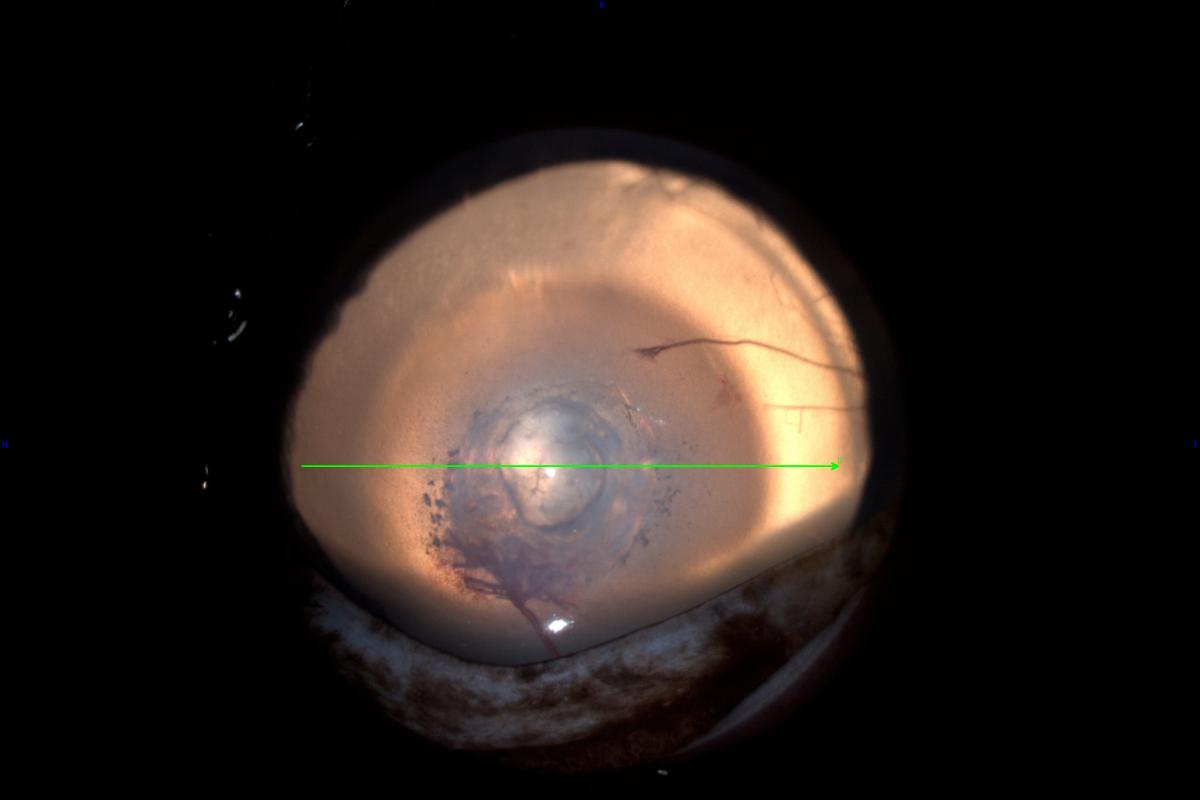

Con amplia experiencia en cirugía corneal, AniCura Ocaña Oftalmología Veterinaria ha intervenido recientemente a un perro de 14 años con degeneración corneal cálcica, una patología frecuente en perros de edad avanzada y asociada a inflamación ocular. Antes de la intervención, los especialistas del centro decidieron someter al paciente a un estudio con tomografía de coherencia óptica (OCT), una técnica de diagnóstico por imagen de alta resolución que aporta, en tiempo real, información cuantitativa y cualitativa de todas las capas de la córnea.

"La ausencia de contacto con la superficie corneal y la rapidez en la adquisición de imágenes hacen que la OCT sea el tipo de examen más adecuado para estas situaciones, en las que la córnea esté muy comprometida y en un estado de gran fragilidad", asegura Javier Esteban Martín, Practice Manager del centro. "Con el apoyo de un oftalmólogo veterinario y un anestesista, realizamos la OCT bajo sedación. El estudio nos permitió localizar con detalle una bulla corneal intraestromal y la distribución exacta de los minerales de calcio asociados a la degeneración. De esta manera, se pudo delimitar el área de la córnea que debíamos eliminar mediante queratectomía, así como su profundidad".

El estudio con OCT supone un complemento perfecto a la exploración con lámpara de hendidura, añadiendo información relevante para el diagnóstico, la elección del tratamiento y el seguimiento del proceso de curación. "En el posoperatorio inmediato, también pudimos comprobar con este avanzado medio diagnóstico el resultado tectónico del autotrasplante corneal (transposición corneal). En este procedimiento se reemplazó el área enferma de la córnea, por una del mismo ojo del paciente. Es decir, se trasladó la córnea desde la parte superior al centro", indica Javier Esteban.